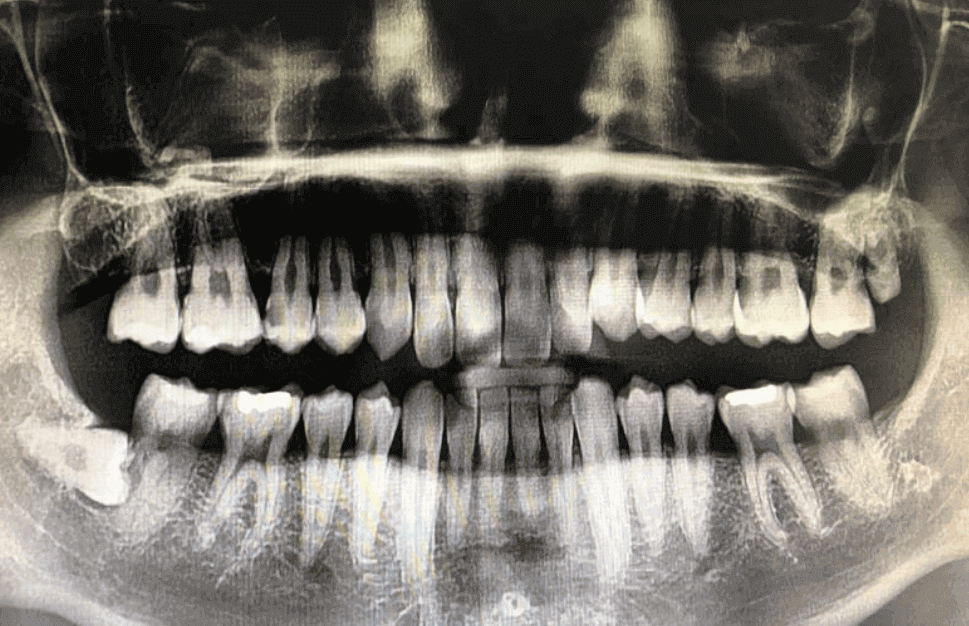

제 현재 상태는 아래와 같습니다.

필요치료 : 임플란트 5개 / 크라운 1개 / 신경치료 2개 / 브리지 1개 / 충치치료 1개

파노라마 엑스레이는 대한민국 국민이라면 건강보험이 적용되는 부분이며, 금액은 병원마다 그리고, 복지가 다른 노인분들과는 차이가 있을 수 있지만 기본 성인 분들이라면 11,000 - 13,000원이 청구되며, 여기에는 기본적인 의사 선생님과 상담까지 포함됩니다.

치과 파노라마 엑스레이 : 건강보험 적용 가능, 11,000원 - 13,000원 실제 청구 비용 발생